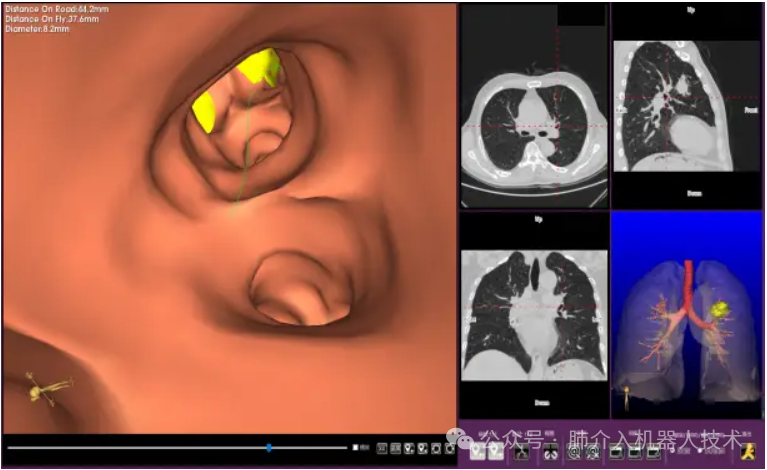

03、奧泰康助力肺部穿刺手術(shù)導(dǎo)航系統(tǒng)獲證

2024年1月31日,經(jīng)國家藥品監(jiān)督管理局公示,蘇州朗開醫(yī)療技術(shù)有限公司自主研發(fā)的肺部穿刺手術(shù)導(dǎo)航系統(tǒng)(國械注準20243010222)獲得NMPA批準上市,奧泰康助力本項目注冊申報服務(wù),系2024年奧泰康助力獲得的首張三類醫(yī)療器械注冊證。